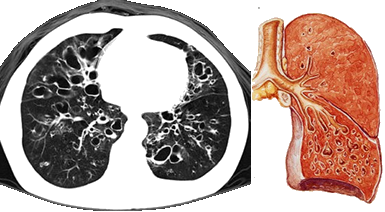

是指各种原因导致的支气管结构破坏,引起支气管异常和持久性扩张。

支气管扩张大多继发于急、慢性呼吸道感染和支气管阻塞。

『答案解析』支气管扩张大多继发于急、慢性呼吸道感染和支气管阻塞。